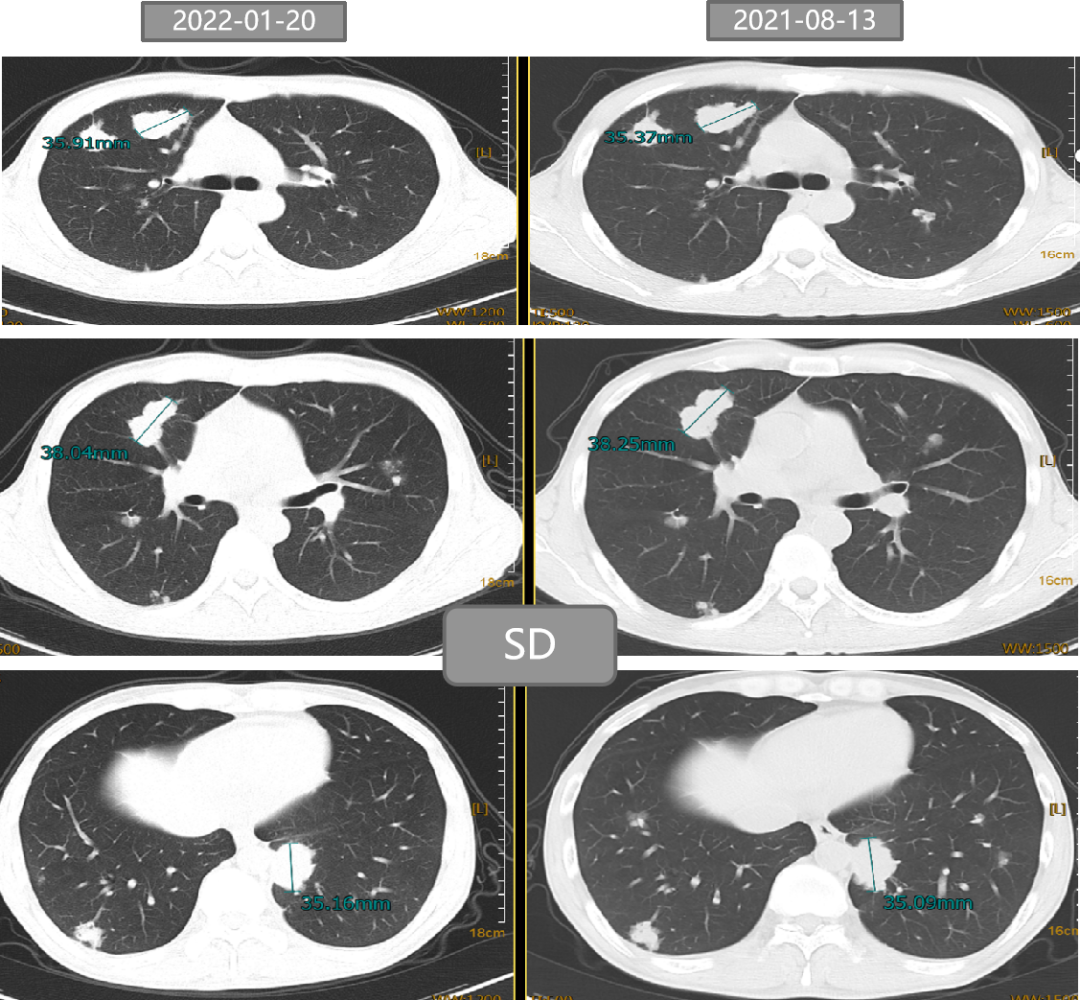

二 病例分享 专家简介 01 基本情况 刘某某,男性,28岁。 主诉:大便次数增多2月。 首诊时间:2018-07-03,北京大学人民医院。 既往史:右踝关节骨折术;痔疮病史。 个人史:无特殊。 家族史:其父为小细胞肺癌患者。 入院查体:ECOG 1分,无明显阳性体征。 02 初诊病史 肿瘤标志物:CEA 19.45 ng/ml。 肠镜及病理:直肠(距肛门约8cm处),直肠腺癌。 胸腹盆增强CT:1.双肺多发结节,考虑转移瘤可能性大;2.肝S6段异常密度灶;3.下段直肠癌可能性大。 盆腔增强MRI:(中位)直肠癌、T(3b)、N(2b)、癌结节(0)、CRM(阳性)、EMVI(阴性)、非区域淋巴结(阴性)。 上腹部增强MRI:肝S6段小结节,不典型血管瘤可能大。 初步诊断: 1.直肠癌(cT3N2bM1aIVA期 )肺转移; 2.痔疮; 3.右踝关节骨折术后; 4.肝血管瘤。 03 治疗方案 外院:XELOX。 我院首诊:2018-07-18。 免疫组化:MLH1(+),PMS2(+),MSH2(+),MSH6(+)。 2018-07-25至2018-09-26 XELOX *2+局部放疗*25f,PD。 基因检测(2018-10-23):KRAS、NRAS、BRAF基因均未见突变。 二线治疗:2018-10-18至2019-03-01 贝伐珠单抗+FOLFIRI*9 (SD→PD)。 疗效评估 三线治疗:2019-03-28至2019-07-23 西妥昔单抗+伊立替康+雷替曲塞*6(SD→PD)。 疗效评估 2019-07-25 瑞戈非尼 80mg po。 2019-09-26 复查:SD,瑞戈非尼 120mg po。 2019-11-21 复查:PD,瑞戈非尼 160mg po。 疗效评估 2019-12-19 至2020-09-24 信迪利单抗 200mg q3w +瑞戈非尼80mg po d1-d21 q4w。 2020年 ASCO 更新的瑞戈非尼+纳武利尤单抗(regorafenib+nivolumab)在晚期结直肠癌或胃癌患者中的Ib期临床试验(REGONIVO, EPOC1603)。 疗效评估 2020-09-26 盆腔增强MRI:直肠癌治疗后复查,与2020-05-10 MRI比较:直肠壁增厚程度较前似进展;直肠下段偏左侧新发不规则异常信号,考虑瘘管/脓肿形成。 考虑直肠下段脓肿,行抗感染治疗。 并于 2020-10-14 在气管插管全身麻醉下行腹腔镜下乙状结肠造口术。 2020-11-06 至2021-02-05 信迪利单抗200mg q3w+呋喹替尼3mg d1-21 q4w。 双肺多发转移瘤,对比 2020-11-04 CT较前增大、部分空洞形成。 TAS-102:新型口服细胞毒性药物 2021-V1版NCCN指南和2021 CSCO指南推荐更新:TAS-102±贝伐珠单抗(Bev)作为mCRC三线标准治疗。 2021-02-05 至今 TAS-102 60mg bid d1-5,d8-12,q4w 联合信迪利单抗200mg q3w。 不良反应 西妥昔单抗:皮疹; 瑞戈非尼:手足综合征; PD-1抑制剂:免疫性甲状腺炎; TAS-102:骨髓抑制(中性粒细胞IV度下降、贫血)。 04 诊疗小结